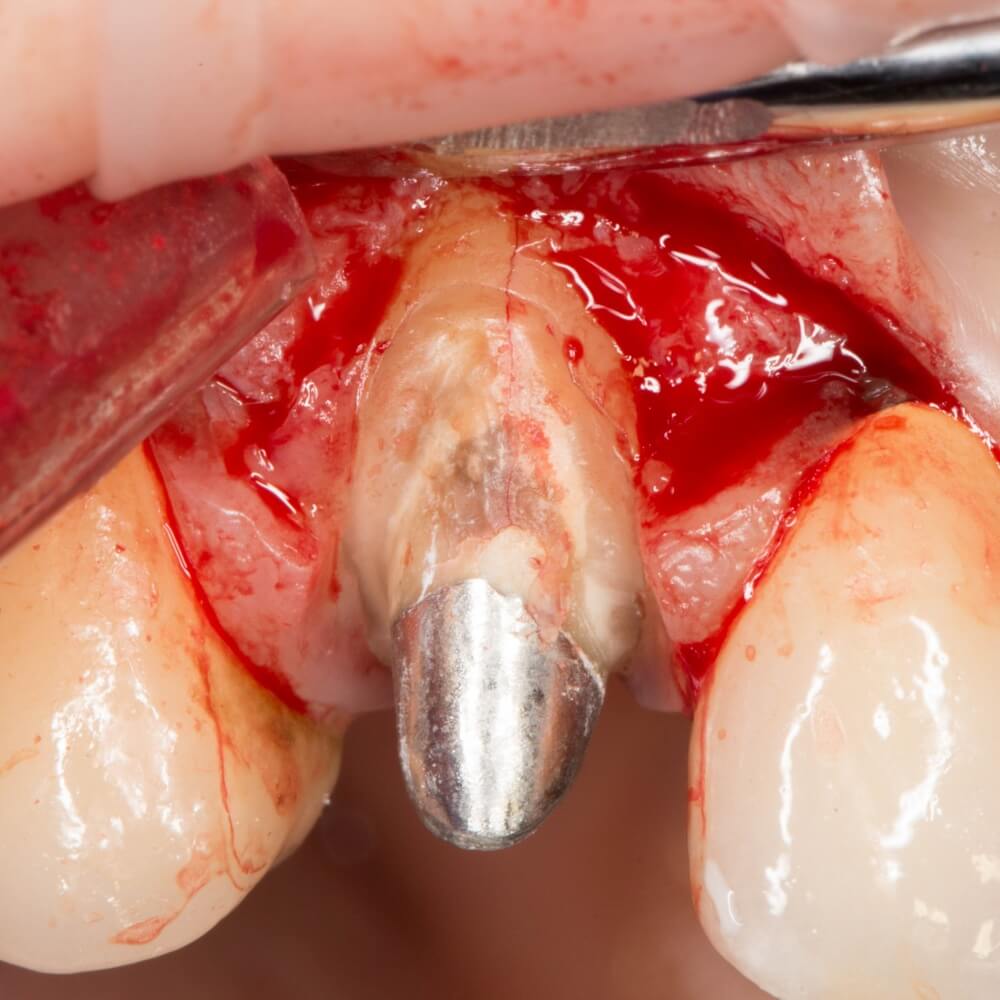

Рекомендации по установке имплантов. Для всех. Часть V.